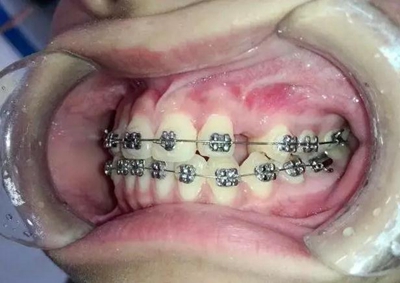

患者13歲,經(jīng)過一段時(shí)間的治療前牙反合已經(jīng)正常,只有左上3尖牙埋伏

手術(shù)切開,去除上部牙槽骨暴露出來牙尖,可以看到尖牙緊緊壓在側(cè)切牙根尖唇面上。

粘上舌側(cè)扣用結(jié)扎絲附弓結(jié)扎